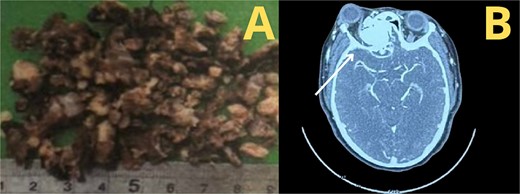

According to the information gathered, the surgeon decided to perform a partial resection of the maxillary neoplasia (Fig. 2). The chosen approach upon evaluation was the Caldwell–Luc procedure, gaining access to the maxillary sinus. Dimensions and anatomic relationships of the mass were established, determining an extension up to the sphenoid bone covering the ipsilateral choana. A predominantly osseous tumor was observed, with a significant contribution of trabecular bone, vascularized, exhibiting a tendency to hemorrhage. Partial resection of the tumor was accomplished, leading to visualization of the peripheral orbit but not decompressing it totally due to hemodynamic instability during intervention. A residual mass was left at the sphenoidal level and cranial base, a future reintervention was considered.

Postoperative outcomes and pathology report

A second intervention was performed with the Caldwell–Luc approach for complete tumor removal.